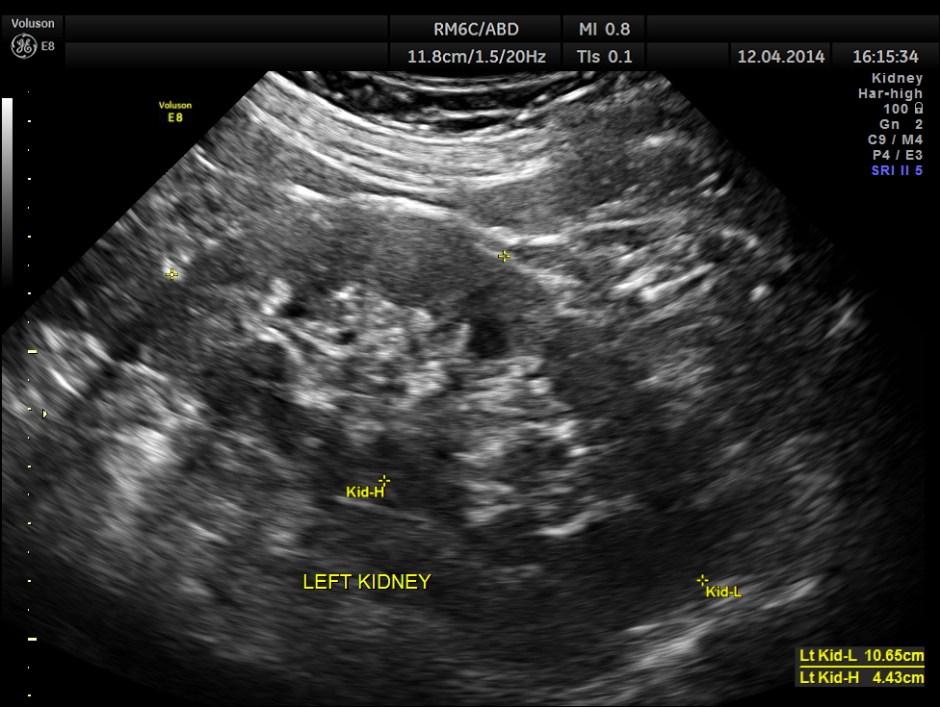

Both the kidneys appeared to be normal . No calculus was seen . There was no evidence of any obstruction.